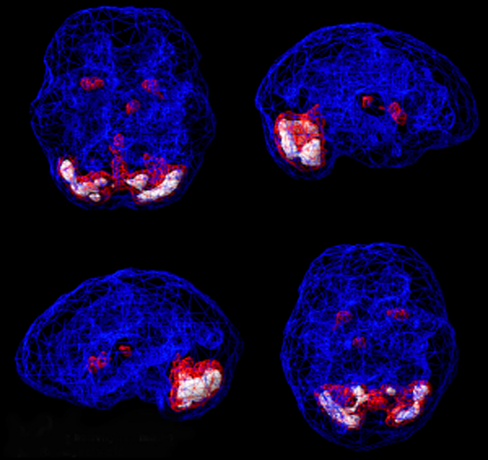

Brain SPECT Images

HEALTHY SURFACE RENDERING

Healthy 3D SPECT, looking at the top 45% of brain perfusion, anything below that level shows up as a hole or a dent.

HEALTHY ACTIVE RENDERING

Blue equals average perfusion, red equals the top 15% of perfusion and white is the top 8%.

TOXIC SURFACE SCAN

Notice the “Swiss cheese,” shriveled appearance,

indicating areas of decreased perfusion.

TRAUMA SURFACE SCAN

Asymmetrical decreased perfusion left frontal

temporal lobe.